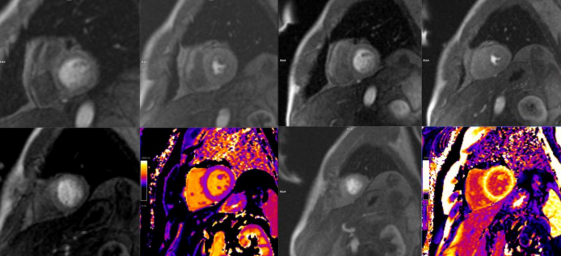

Recientemente el Hospital Universitario Quirónsalud Valle del Henares realizaba su primera resonancia cardíaca de perfusión, también llamada resonancia de estrés.

Como destaca la Dra. Angélica Romero Daza, Jefa de la Unidad de Imagen Cardíaca Avanzada, «la resonancia de perfusión miocárdica es una prueba de imagen cardíaca no invasiva, útil en el diagnóstico y valoración de pacientes con cardiopatía isquémica o sospecha de la misma».

Se trata de una técnica con gran evidencia científica que ofrece gran sensibilidad y especificidad a la hora de diagnosticar enfermedad coronaria significativa y su repercusión sobre el músculo del corazón, dado que, además de detectar falta de riego del corazón (isquemia), también aporta información sobre la anatomía, función y cicatrices del mismo. Todo ello con una gran calidad y definición de imagen y sin la necesidad de radiación, por lo que se está convirtiendo en la prueba de referencia para el estudio de la cardiopatía isquémica.

Esta prueba no requiere interpretación del electrocardiograma, por lo que es especialmente útil en pacientes con alteraciones electrocardiográficas que dificulten la interpretación de otras pruebas de detección de isquemia. Para realizarla es necesario administrar, por vía venosa, un agente vasodilatador (regadenoson) seguidamente de contraste de gadolinio y obtener unas imágenes mediante la resonancia para detectar defectos de riego miocárdico.